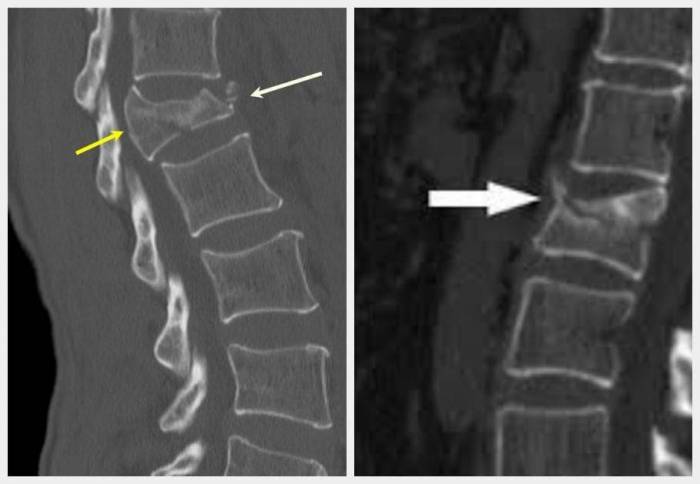

На поздних стадиях остеопороза в клинической картине преобладают признаки поражения позвонков. Происходит компрессия их передних тел, что провоцирует клиновидную деформацию. Сначала деструктивно-дегенеративные процессы затрагивают шейный и грудной отделы позвоночника, а затем распространяются на пояснично-крестцовую область. Характерная особенность симптоматики остеопороза — переломы грудных позвонков происходят незаметно. Иногда возникает незначительная боль, обычно связанная с ущемлением чувствительного нервного окончания.Специфическими признаками остеопороза на позднем этапе развития становятся:

Ведущий симптом остеопороза позвоночника — спонтанный перелом позвонка, не коррелирующийся с тяжестью травмы. Поэтому при повреждениях, не сопровождающихся болью, врачи сразу предполагают снижение костной массы. Когда переломы позвонков поясничного или грудного отдела происходят в результате даже статических нагрузок, пациент обследуется на наличие метастазированных новообразований, «забирающих» кальций из всего опорно-двигательного аппарата. Формирование опухолей, особенно злокачественных, сопровождается специфической симптоматикой.